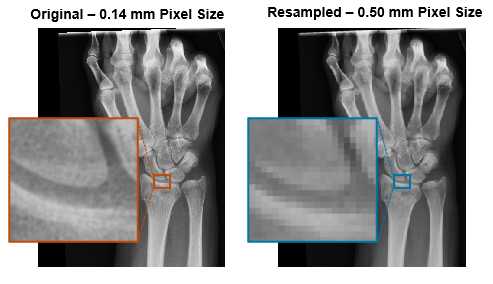

Resampling

Use resampling to change the pixel or voxel size of an image without changing its spatial limits in the patient coordinate system. Resampling is useful for standardizing image resolution across a data set that contains images from multiple scanners.

To resample a 2-D medical image, you can use the imresize

function with a target number of columns and rows. For example, this code shows how to

resample the pixel data in the medicalImage

object medImg to a target pixel size, specified by

targetPixelSpacing.

ratios = medImg.PixelSpacing./targetPixelSpacing;

targetSize = ceil(ratios.*size(medImg.Pixels)); % in pixels

resamplePixels = imresize(medImg.Pixels,targetSize);Define the spatial referencing of the original and resampled images by using the imref2d object.

originalR = imref2d(size(medImg.Pixels),medImg.PixelSpacing(1),medImg.PixelSpacing(2)); resampledR = imref2d(size(resamplePixels),targetPixelSpacing(1),targetPixelSpacing(2));